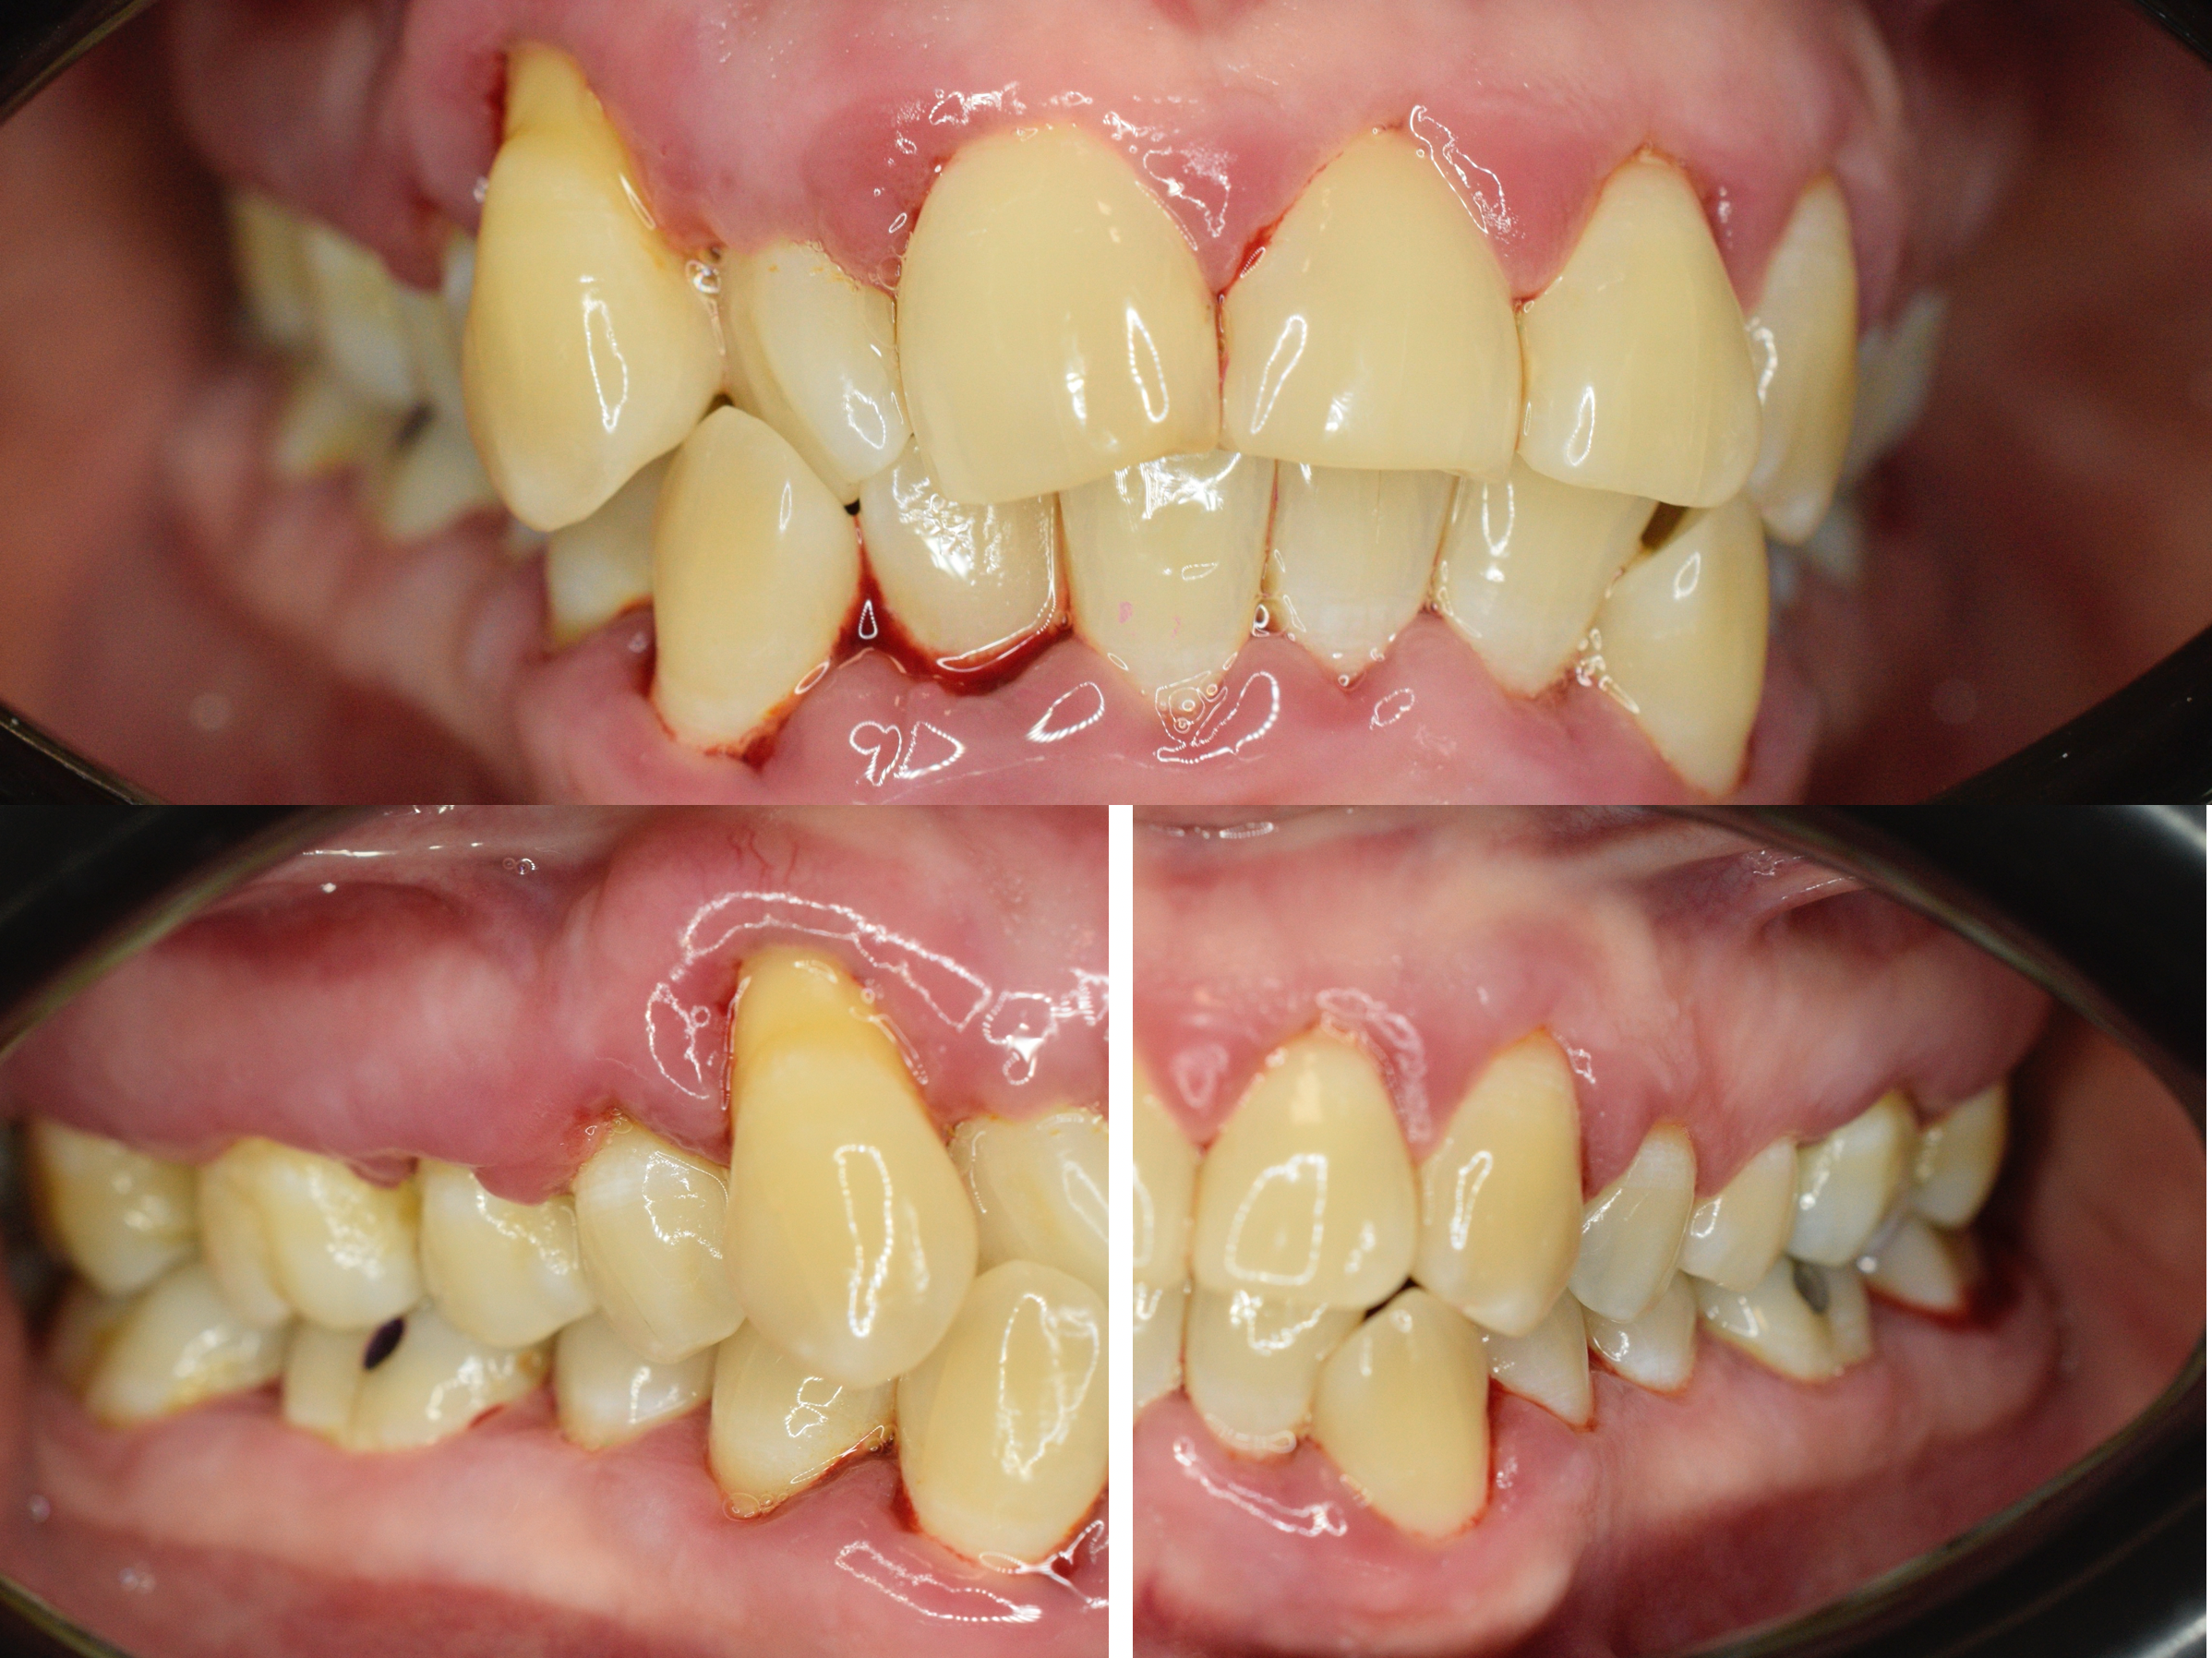

Le immagini cliniche del prima e dopo trattamento e il test di placca al 100% che accompagnano questo articolo mostrano visivamente quanto sia determinante il controllo del biofilm nella guarigione dei tessuti.

Prima e dopo: cosa dimostrano le immagini

Le fotografie cliniche allegate mostrano:

• Gengive infiammate e sanguinanti prima della terapia

• Riduzione dell’edema e dell’eritema dopo la decontaminazione

• Miglioramento della salute gengivale senza incisioni chirurgiche

L’immagine del test di placca al 100% è particolarmente significativa: quando tutto è colorato, significa che il biofilm è ovunque. È da lì che bisogna partire.